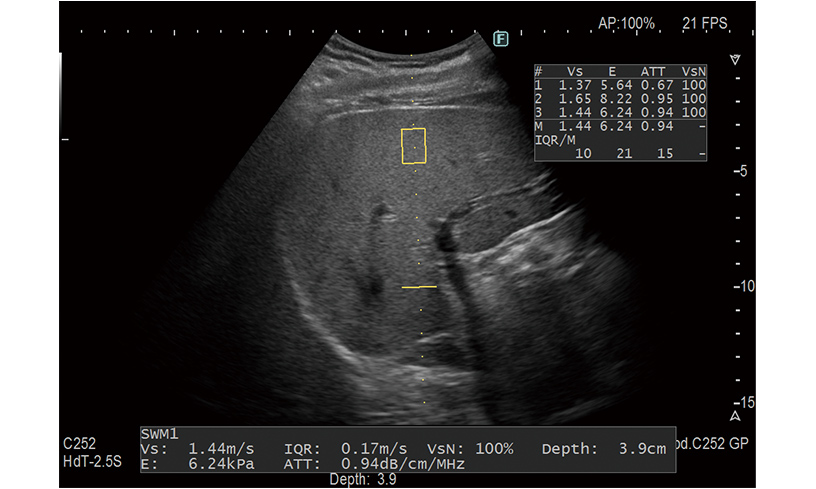

肝硬度・線維化・脂肪化測定

Shear Wave Measurement(SWM) / Attenuation計測(ATT)

組織にせん断波を発生させ、伝搬速度(Vs)を計測することで硬さを定量的に評価できます。肝脂肪化の程度を推定するための指標(ATT)も同時に計測します。

慢性肝障害のある方・脂肪肝がある方